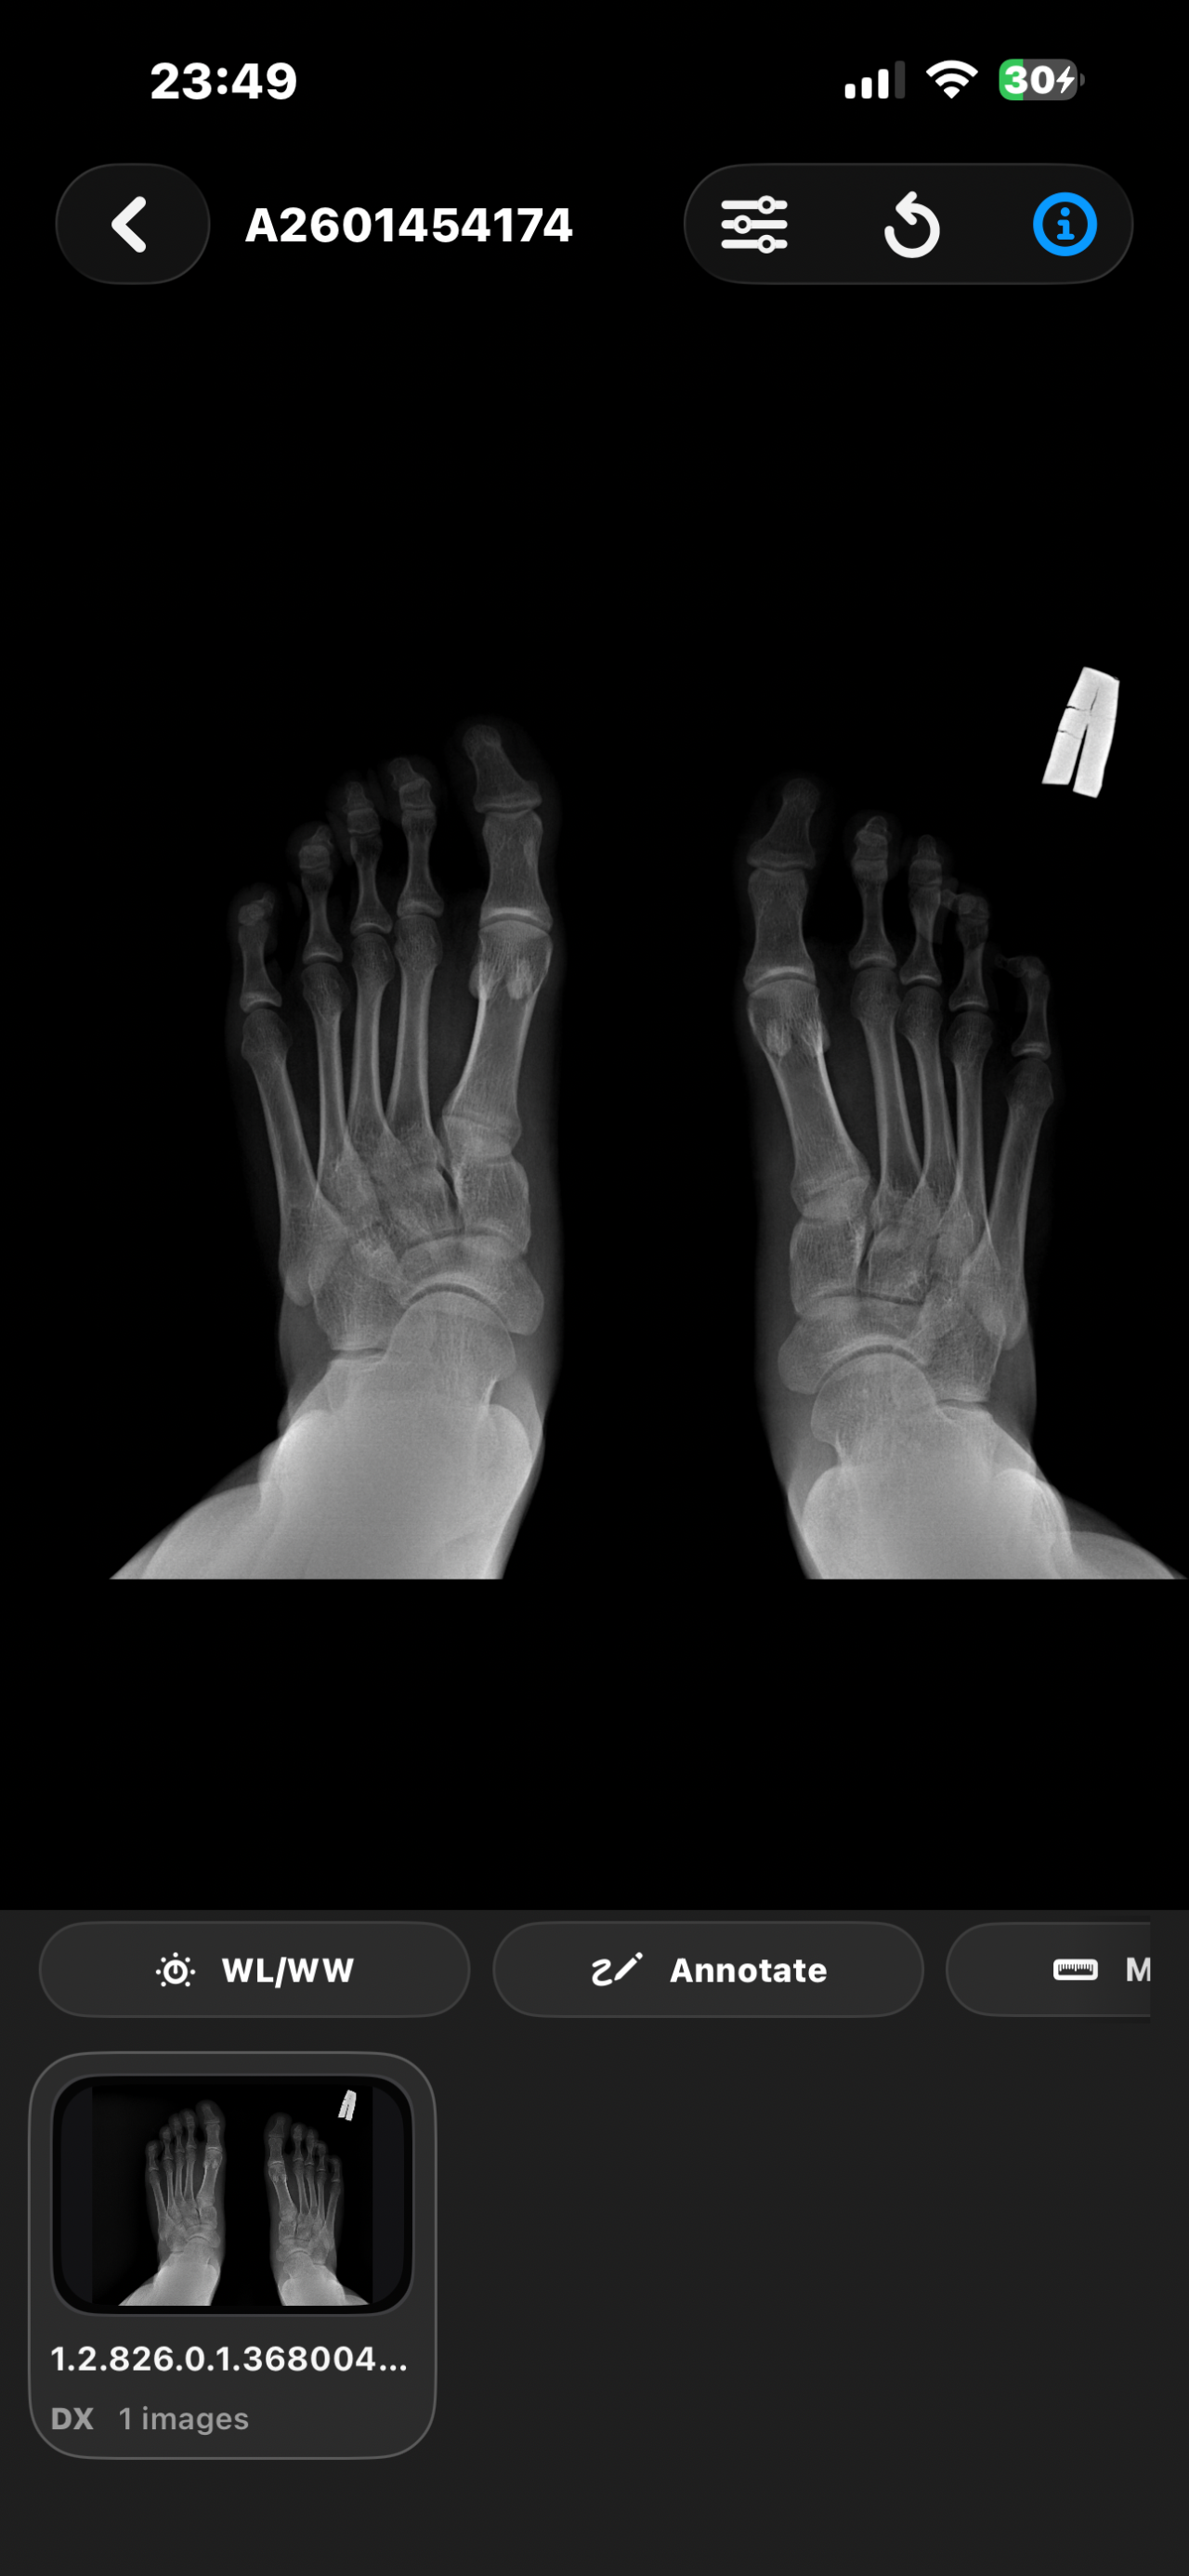

Открыты ли зоны роста. Смогу еще вырасти?

Здравствуйте, мне 16 лет и рост ~173см и мне очень хотелось бы узнать, открыты у меня зоны роста или нет? Сверстники все по 180-185 см и на их фоне я чувствую себя не очень комфортно. Сколько сантиметров я смогу прибавить в росте? Спасибо за ответ!